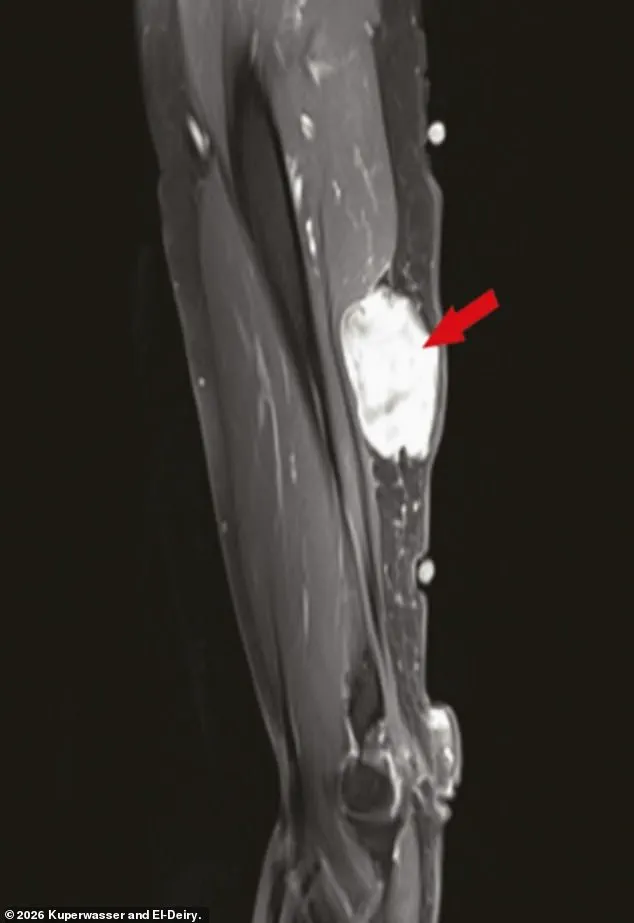

El-Deiry and Kuperwasser’s analysis also uncovered several intriguing case reports.

These included instances of tumors developing near injection sites in the arm, a phenomenon that the authors suggested warranted further investigation.

Additionally, the study identified cases where slow-growing cancers that had previously been stable appeared to ‘flare up’ after vaccination.